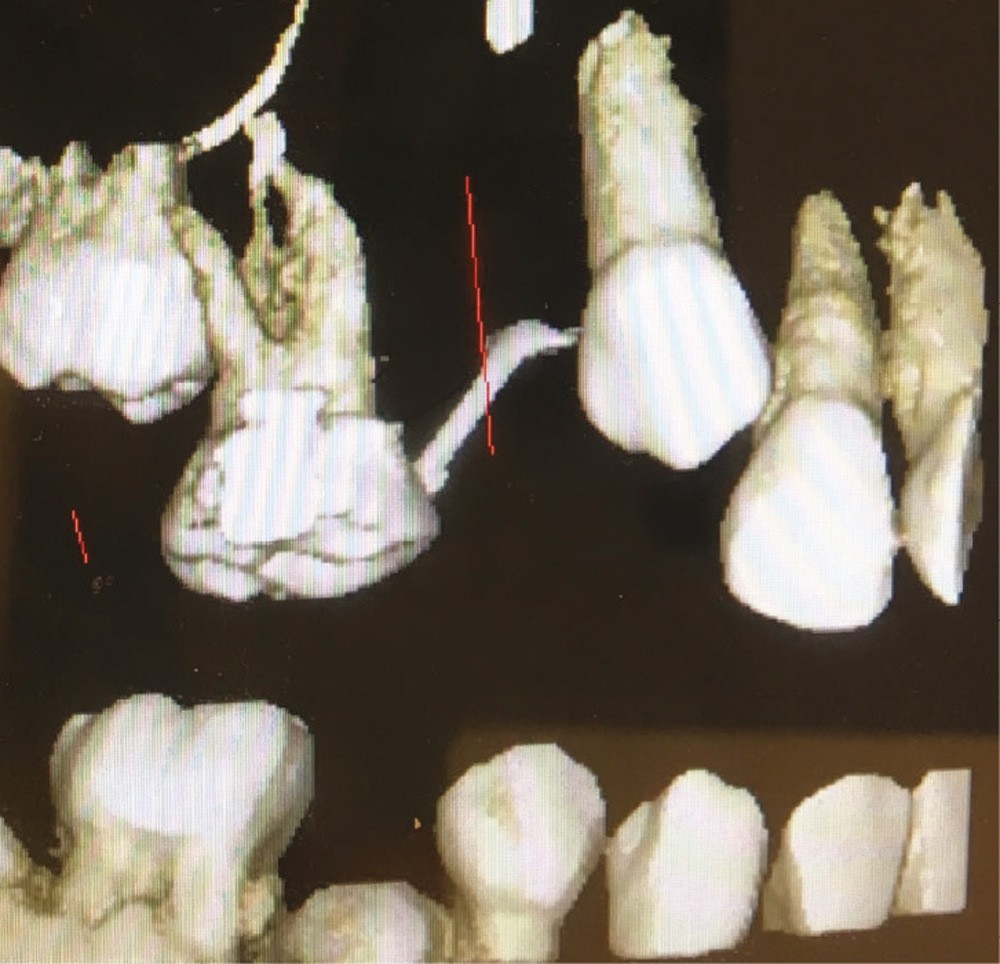

Un bilan radiologique 3D (Cone Beam CT) est prescrit dans le but d’évaluer, avec l’équipe de chirurgie du Dr Jean-Luc Charrier (Hôpital Bretonneau), la possibilité de transplantation d’une prémolaire du secteur 4 vers le secteur 1 et de définir le meilleur transplant possible entre 44 et 45. Sont analysées les dimensions du site receveur ainsi que l’anatomie, la position et l’état de maturation radiculaire des prémolaires candidates à la transplantation (fig. 3).

Cet examen nous apprend que :

- concernant le site receveur : son volume osseux est suffisant pour accueillir une des prémolaires du secteur 4 ;

- Concernant 45 :

- sa situation endo-osseuse (à l’abri de la flore bactérienne buccale et avec un desmodonte immature car non soumis aux stimuli occlusaux, facilitant une avulsion atraumatique) et son immaturité radiculaire franche (apex largement ouvert favorisant la revascularisation) font d’elle un transplant de choix ;

- mais il existe une proximité nette entre la couronne de 45 et la racine de 44, (augmentant le risque de lésion de 44 lors de l’avulsion de 45), et un rapport étroit entre la couronne de 45 et la corticale osseuse vestibulaire (augmentant le risque de lésion parodontale post-extractionnelle) ;

- enfin, 45 présente une longueur radiculaire encore courte risquant d’amener à un rapport couronne/racine limite in fine si l’édification radiculaire devait être stoppée après la transplantation de cette dent ;